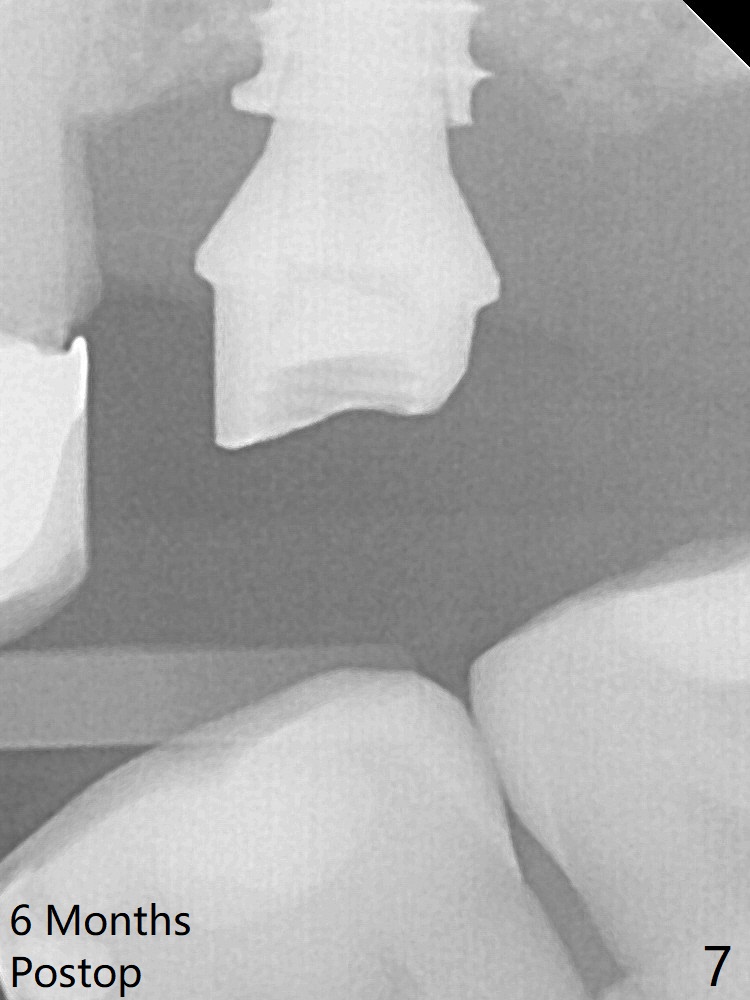

Following minimal use of Magic Lifter, Vanilla Graft is inserted (Fig.4 *) and a 4x9 mm dummy implant is placed partially.  It appears that the implant is a little too long.  After placement of more allograft (Fig.5 *), a 5x7 mm implant is placed with ~ 35 Ncm.  With placement of a 5.5x4(2) mm abutment, an immediate provisional is fabricated to close the socket.  Six months postop, the bone graft remains in the sinus around the apical end of the implant (Fig.6 *), while there seems no bone loss coronally (Fig.7).

In fact there is, as shown later (Fig.8-11 < and lingual (L)).